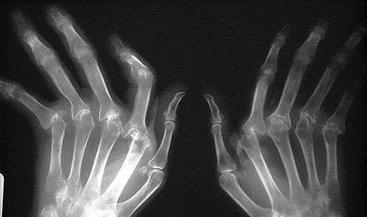

生物3D科技公司Organovo最近宣布與加利福尼亞大學達成合作。UCSF正在努力開發(fā)先進的生物3D打印組織,這一研究將用于骨骼疾病的治療。